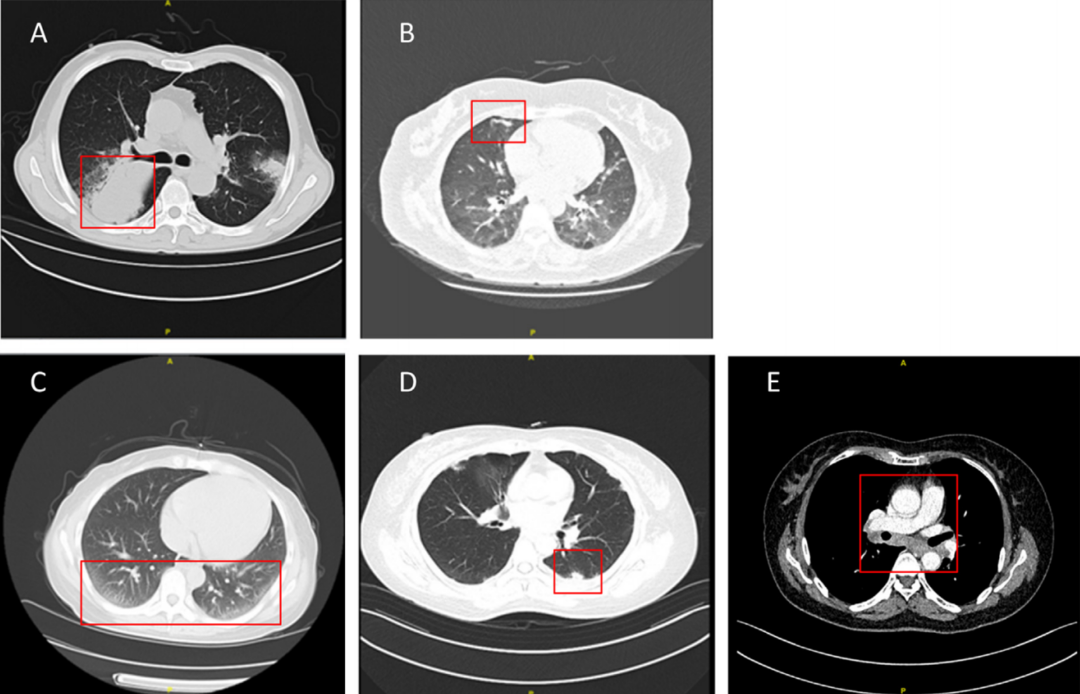

惠普尔养障体阳性患者的影像学表现呈现多样化特征,其中最常见的类型依次为结节(54%)、斑片影(52%)、磨玻璃影(35%)和肿块(24%)(表4)。肺炎患者的代表性影像学表现总结于图3。这种影像学上的多样性使得该病难以仅凭影像学特征与普通肺炎相鉴别,这也是其易被误诊或漏诊的重要原因之一。

图3 惠普尔养障体肺炎的影像学表现,包括肿块(A)、斑片影(B)、磨玻璃影(C)、结节(D)及纵隔淋巴结肿大(E)。